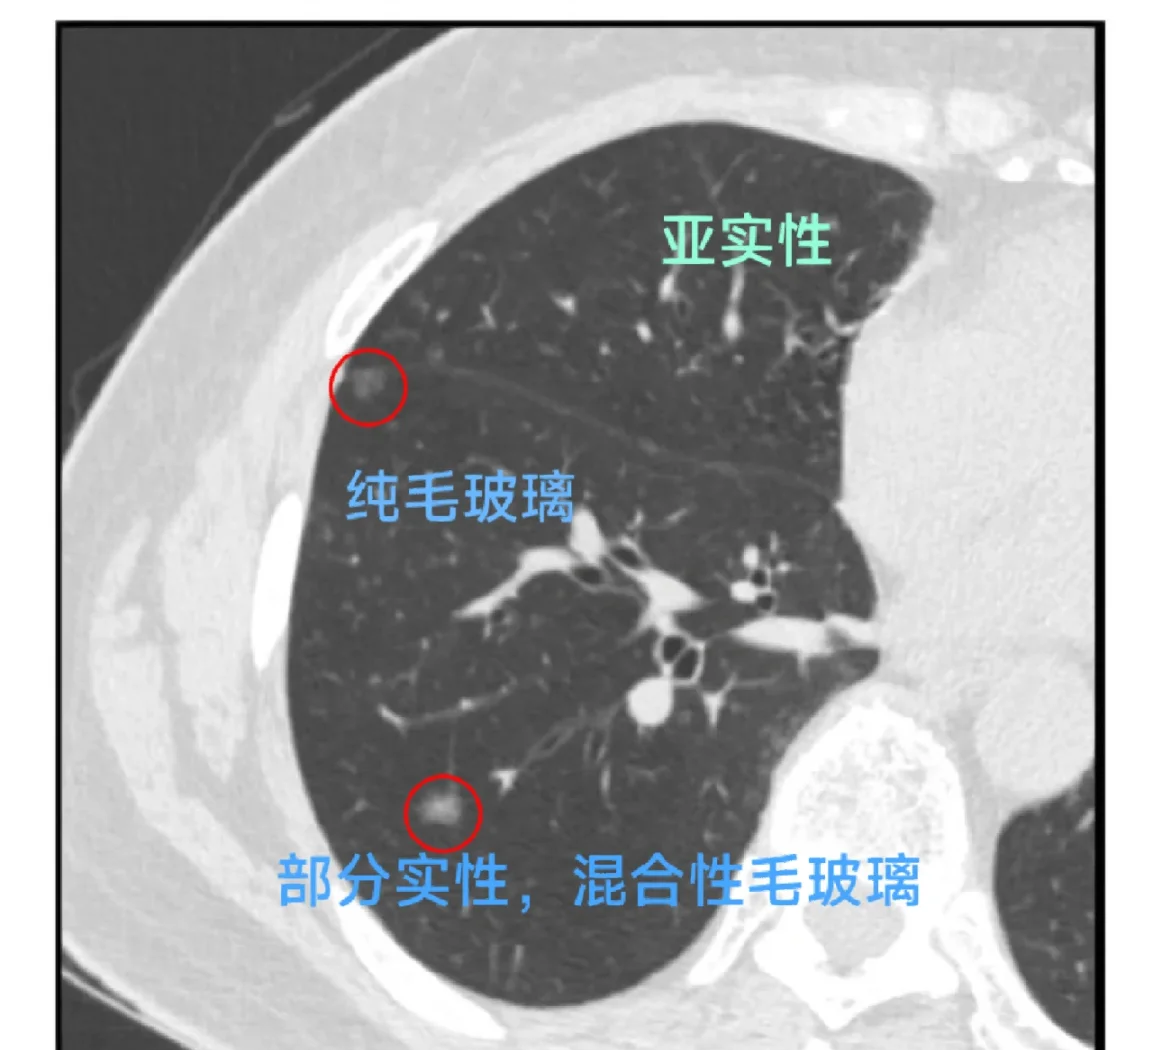

胰岛素水平从18→7μU/mL 肺磨玻璃结节密度降低 餐后困倦感消失(胰岛素波动平稳的标志)